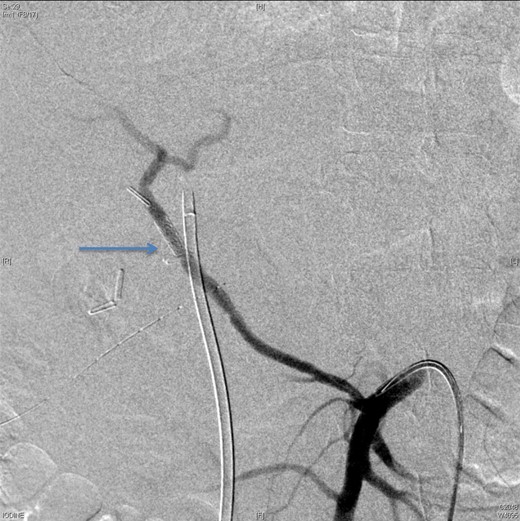

On Day 7, the patient bled again from the same aneurysm of the left hepatic artery. A repeated angiography revealed the bleeding with a reduced flow in the stented, replaced right hepatic artery (Fig. 4). The active bleeding was stopped using gel-foam embolization of the two branches of the left hepatic artery (Fig. 5) with a decision to embolize the whole left hepatic artery if bleeding did not stop while holding the heparin infusion. The patient's liver function was preserved, and the bleeding stopped despite anticoagulation.

An angiographic scan showed reduced flow in the stented replaced right hepatic artery.